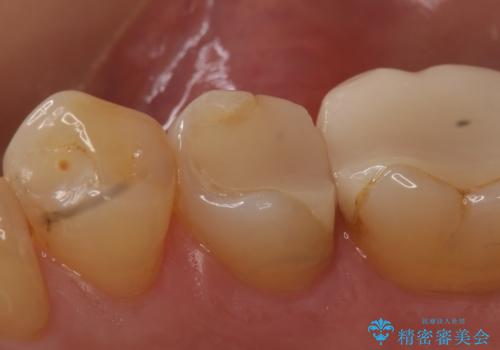

今回用いたオールセラミッククラウンはジルコニアフレームという白い素材の上にセラミックを盛っているため、審美性が非常に高いのが特徴です。

また、ジルコニアは人工ダイヤモンドの材料にも使われているほど高い強度を持っており、そのためオールセラミッククラウンは審美性だけでなく、奥歯やブリッジの補綴も可能とするクラウンです。